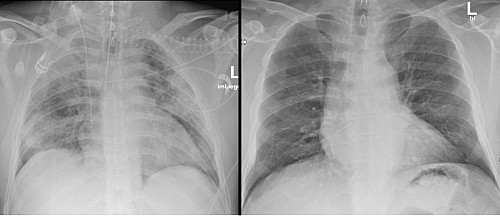

Beschreibung: Fleckige Verschattungen in beiden Lungenlappen als Korrelat der Lungenbeteiligung einer COVID-19-Pneumonie (links) gegenüber einer gesunden Lunge (rechts) erkennen.

Seit Beginn der Corona-Pandemie werden Bildgebungsverfahren – wie Röntgen- oder CT-Aufnahmen – für die Diagnose von SARS-CoV-2 genutzt. Mithilfe radiologischer Bildgebung kann eine Corona-Infektion sicher erkannt und bewertet werden. Zudem sind bildgebende Verfahren schnell und es können präzise Aussagen über die schwere und den Verlauf der Infektion getroffen werden. Um radiologische Daten von COVID-19 Fällen strukturiert erfassen und verarbeiten zu können, haben die 36 deutschen Universitätskliniken gemeinsam mit dem Deutschen Krebsforschungszentrum, dem Fraunhofer-Institut für Digitale Medien MEVIS Bremen, der TU Darmstadt und der Firma mint Medical GmbH, Heidelberg das radiologische Netzwerk RACOON gegründet. Ziel des bundesweiten Netzwerkes ist es, die Datengrundlage zur Erforschung von COVID-19 sowie anderen vergleichbaren Lungenerkrankungen aufzubauen und voranzutreiben. Die gewonnenen Daten sollen zur Weiterentwicklung Künstlicher Intelligenz (KI) verwendet werden. Durch KI-basierte Auswertung der Bildbefunde können schnell umfassende Erkenntnisse gewonnen werden, die zur Bekämpfung der Pandemie und zur bestmöglichen Versorgung von COVID-19- Erkrankten beitragen. Sie stellen zudem eine Basis für Lageeinschätzungen, zur Erstellung von Frühwarnmechanismen und für epidemiologische Studien dar. Im Fokus eigener Forschungsprojekte im RACOON Netzwerk steht am Universitätsklinikum Ulm die Entwicklung und klinische Überprüfung KI-basierter Prädiktionsmodelle für den klinischen Verlauf einer COVID-19 Erkrankung. „Auf dem Röntgenbild wie dem CT-Bild wird die Infektion sichtbar. „Im CT-Bild zeigen sich typischerweise sogenannte milchglasartige Veränderung beider Lungenflügel“, erklärt Professor Meinrad Beer, Ärztlicher Direktor der Klinik für Diagnostische und Interventionelle Radiologie am Universitätsklinikum Ulm (siehe CT-Bild-UKU.jpg). „Die KI wird nun so trainiert, dass sie erkennt wie schwer die Infektion ist und welcher Teil der Lunge befallen ist. Die hierdurch gewonnenen Erkenntnisse stellen einen wichtigen Beitrag zur Optimierung der Therapie von Covid-19-Patient*innen dar“, ergänzt der Radiologe. Auch im Röntgenbild kann man Veränderungen der Lunge bei einer COVID-19-Pneumonie erkennen (siehe Röntgenbilder-UKU.jpg). Mehrere Kliniken und Institute arbeiten am Standort Ulm im Rahmen dieses Forschungsprojektes eng zusammen, so neben der Klinik für Diagnostische und Interventionelle Radiologie die Sektion Klinische Infektiologie der Klinik für Innere Medizin III, das Institut für Virologie, das Institut für Medizinische Mikrobiologie und Hygiene, die Klinik für Innere Medizin II , die Klinik für Anästhesiologie und Intensivmedizin, das Institut für Medieninformatik sowie das Institut für Systembiologie.